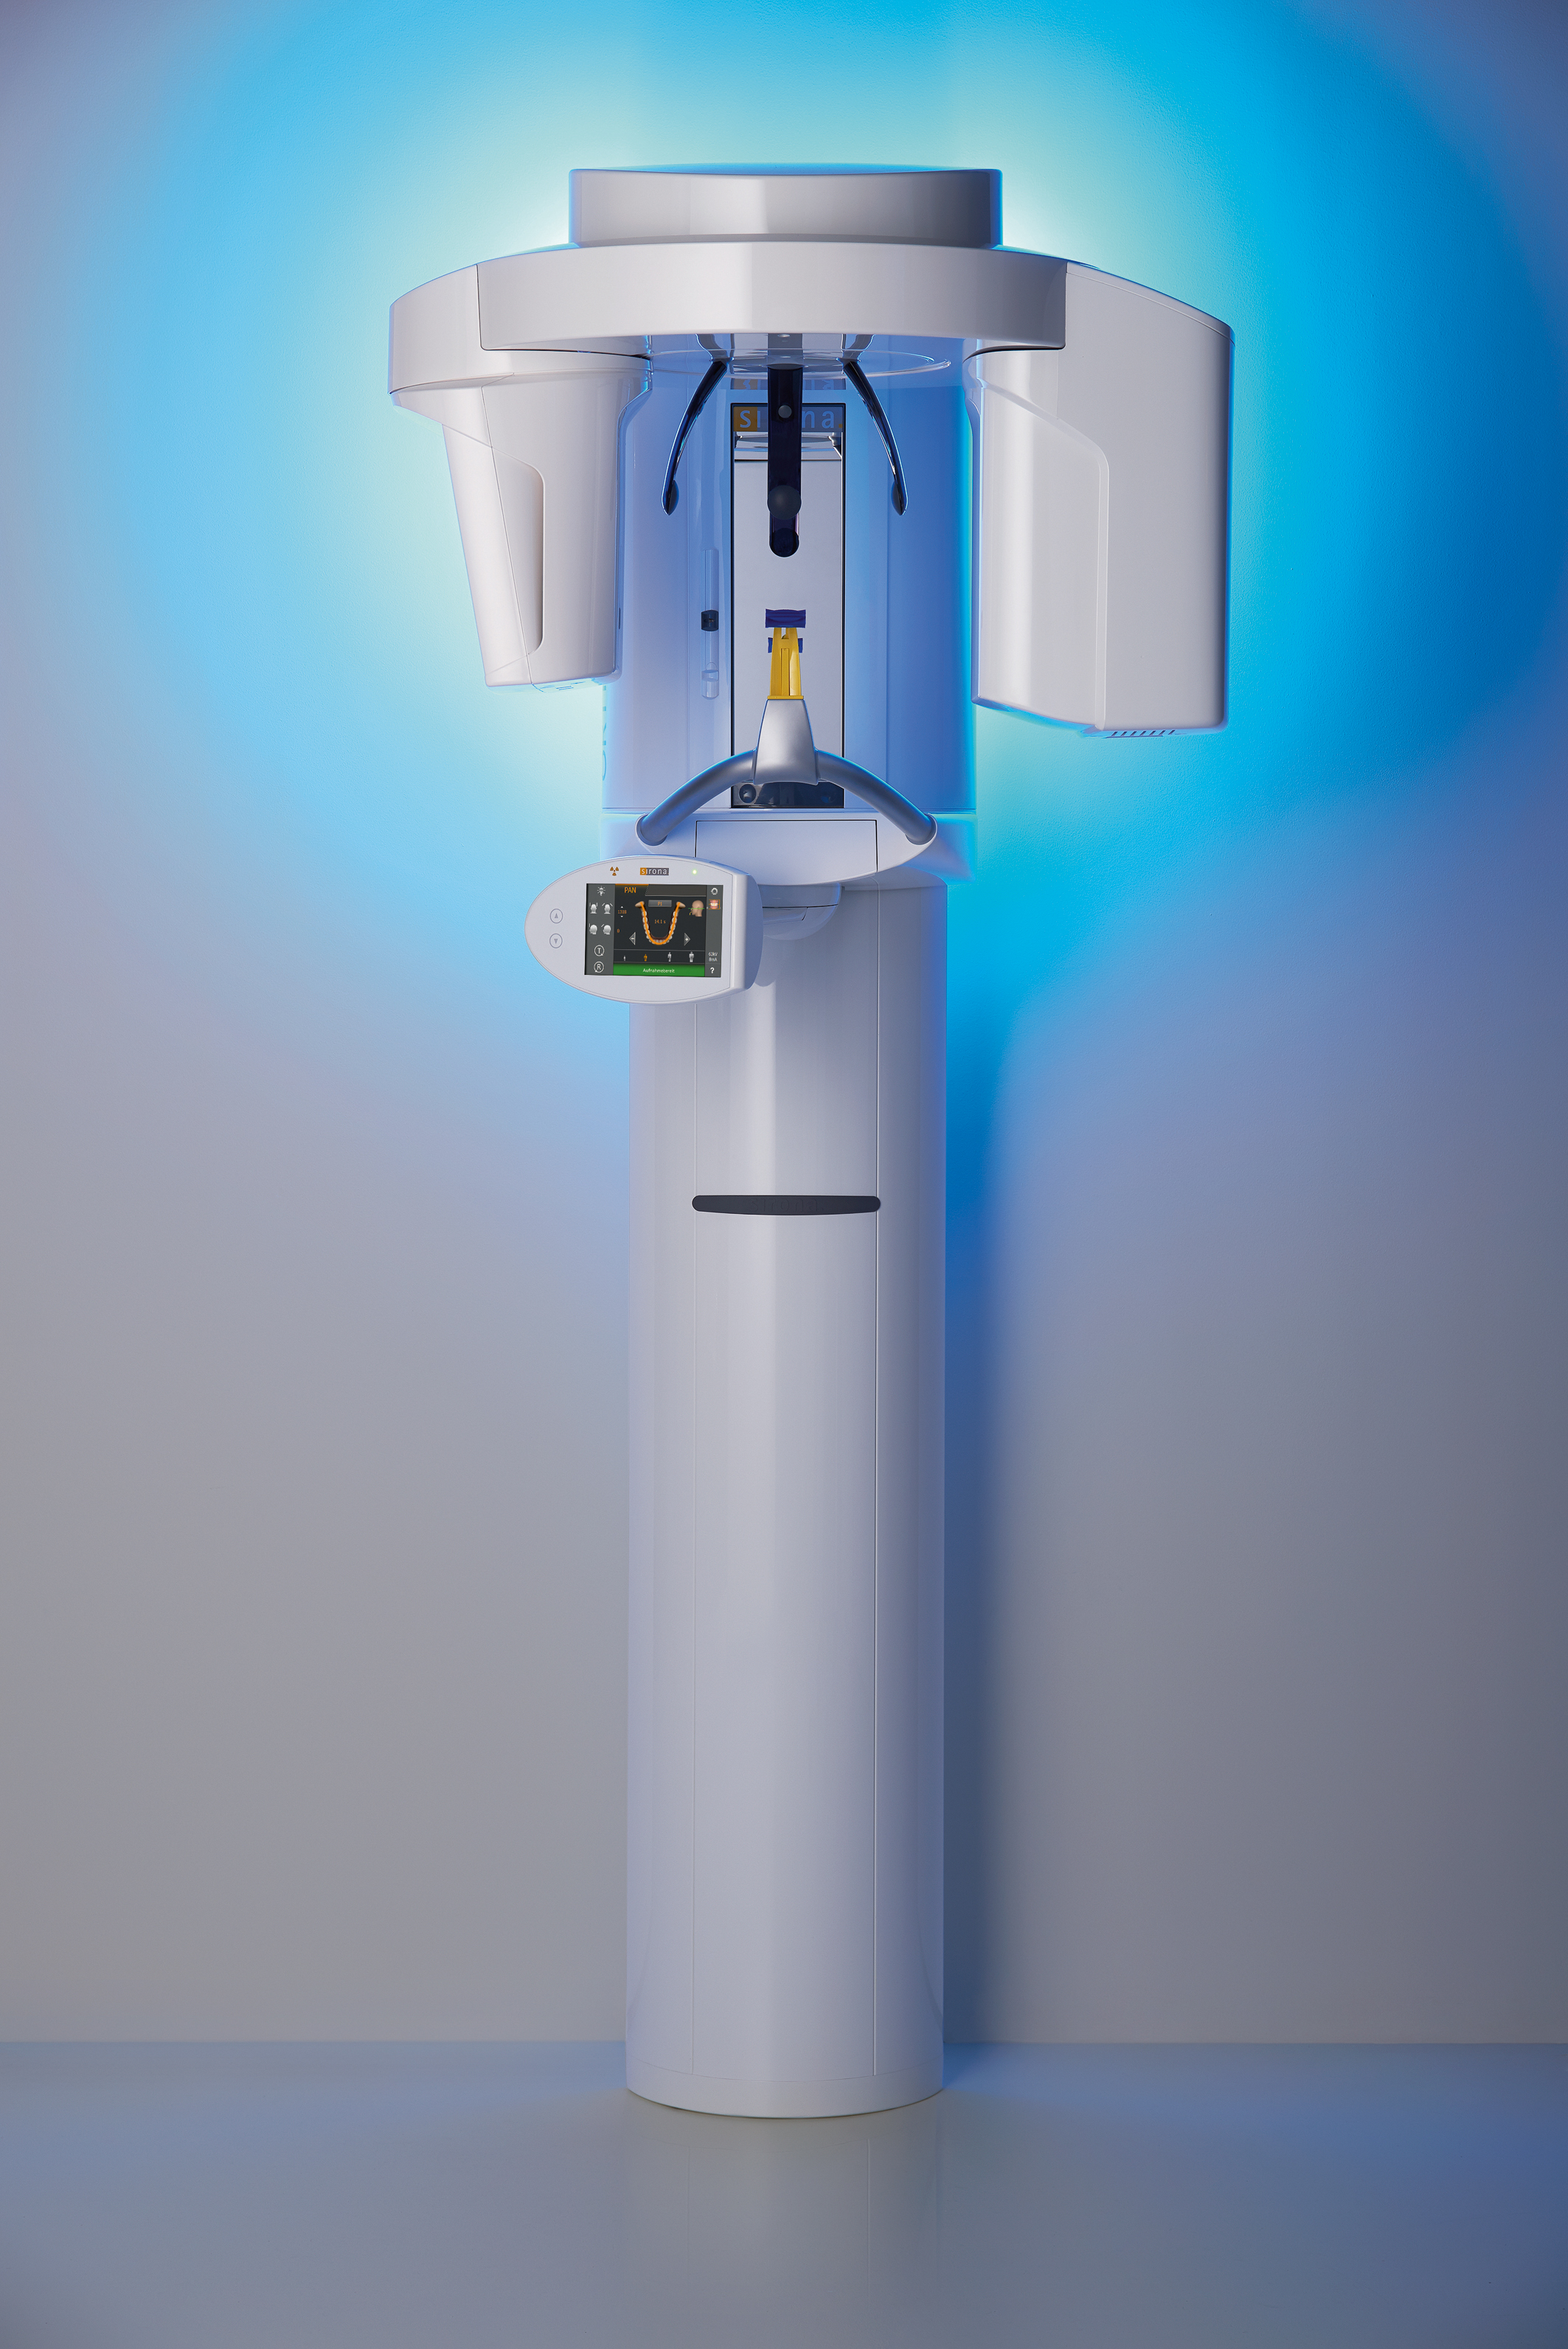

Фотографии и изображения КТ аппарата ORTHOPHOS SL